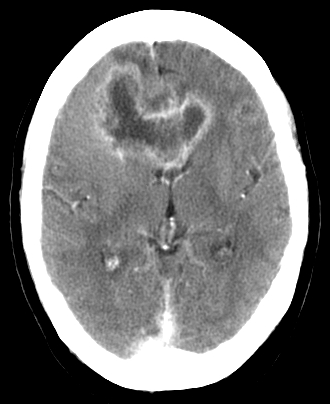

A 5-year-old boy is brought to the office by his parents for evaluation of "clumsiness." The patient's fine and gross motor development have been normal at prior visits, but he now frequently runs into doorways or corners of furniture while walking around the house. He has also begun drinking large amounts of water and urinating "all the time." Temperature is 37 C (98.6 F), blood pressure is 95/65 mm Hg, and pulse is 130/min. Physical examination shows dry mucous membranes and loss of peripheral visual fields. Laboratory results are as follows:

CT scan of the brain (exhibit)

reveals an abnormality. Which of the following is the most likely diagnosis?

A)Craniopharyngioma

B)Medulloblastoma

C)Parasagittal meningioma

D)Pituitary adenoma

E)Rathke cleft cyst

reveals an abnormality. Which of the following is the most likely diagnosis?A)Craniopharyngioma